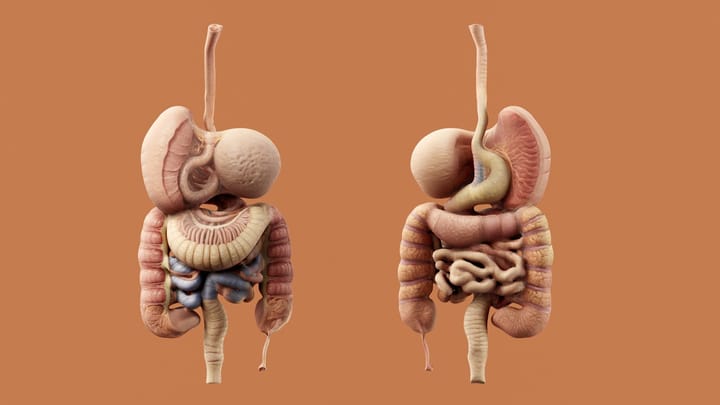

- Srdcová tamponáda: Hromadenie tekutiny okolo srdca ho stláča, čím sťažuje jeho schopnosť pumpovať krv.